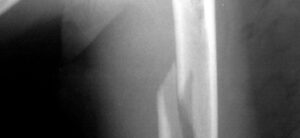

Перелом плеча

Перелом плечевой кости — это повреждение кости, вызванное определенной силой, действующей на эту часть тела. Травмы могут возникать одновременно в нескольких местах плечевой кости. Преждевременное их лечение может привести к серьезным осложнениям, в том числе к инвалидности. Анатомические особенности плечевой кости Плечевая кость условно делится на 3 части: Проксимальный корень. Он является частью плечевого сустава …